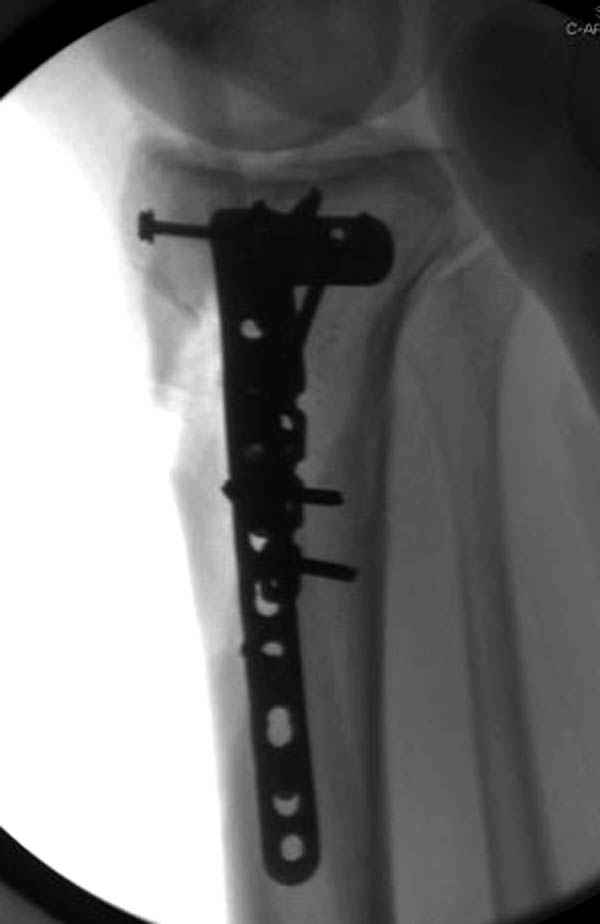

Надеюсь, представленные снимки разных случаев помогут разобраться в тактике, и критика примется без личной обиды.

Вложение не в текстовом формате было извлечено…

Имя     : 15 Med plateau fx.JPG

Тип     : image/jpeg